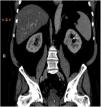

A 67-year-old man with a past history of resected basal cell carcinoma, high blood pressure, and diabetes mellitus was referred to our dermatology department for assessment of lesions on the hands that had appeared 3 months earlier. Physical examination revealed multiple keratotic spines measuring 1mm on the palmar surface of both hands (Fig. 1A and B). Examination of the rest of the skin surface revealed no other significant abnormalities. The patient reported no constitutional symptoms or associated systemic symptoms. With a clinical diagnosis of spiny keratoderma and given that this is considered to be a paraneoplastic skin condition, we performed a battery of tests, which were negative, and full-body computed tomography, which revealed a solid cortical nodule with a maximum diameter of 2cm in the left kidney (Fig. 2); the nodule was resected and histology was compatible with clear cell renal cell carcinoma.